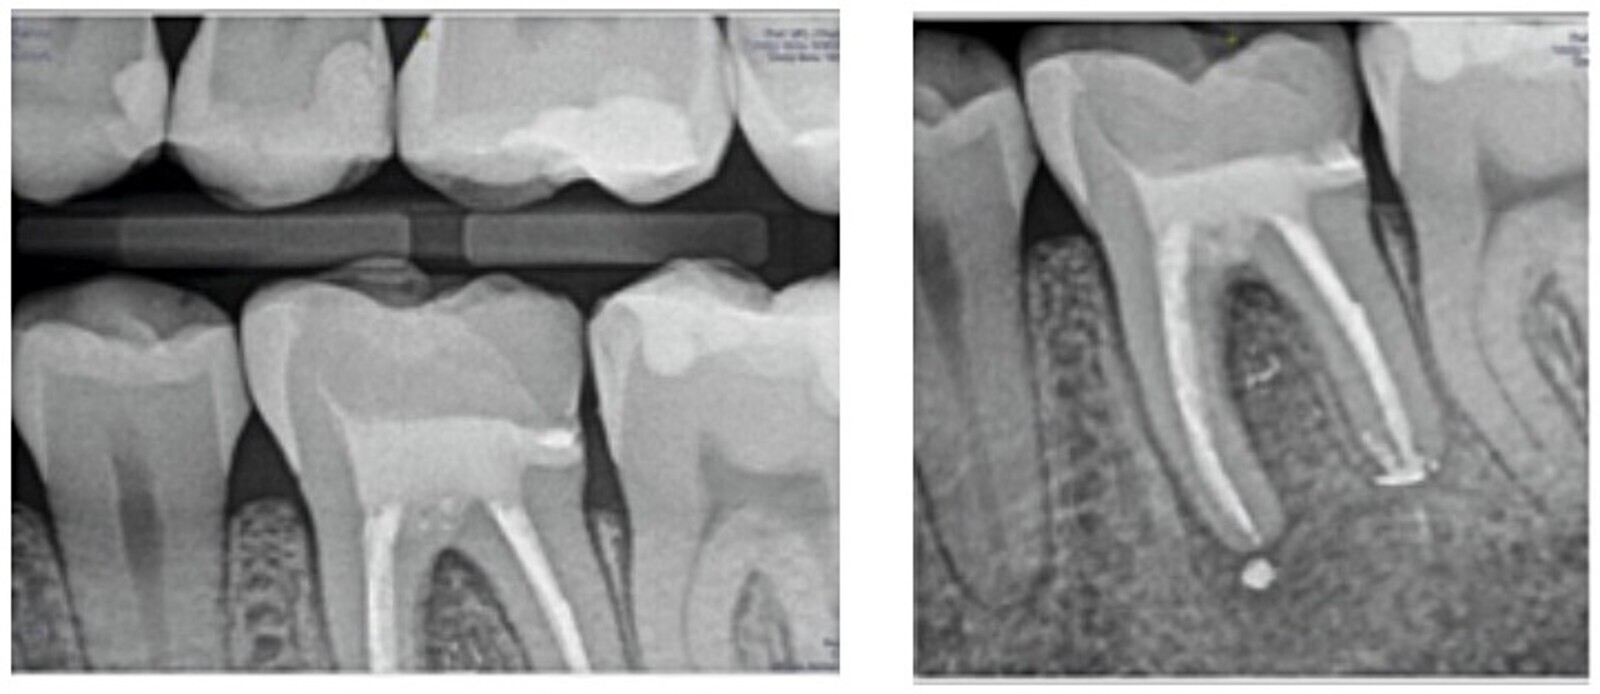

Fig. 2. Radiografía de aleta de mordida y periapical inicial.

Paciente de 27 años de edad que acude a la consulta para salvar un diente. En el examen clínico presenta dolor a la percusión.

Diagnosticamos una periodontitis apical sintomática con un tratamiento de conductos previo. Se decidió realizar la reendodoncia del diente 3.6. y proceder a su restauración definitiva.

Fig. 6. Remoción de la gutapercha y localización de la longitud de trabajo.

La remoción de la gutapercha se llevó a cabo con instrumentación rotatoria complementando la conformación de conducto con un sistema reciprocante.